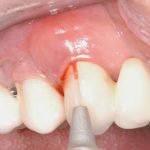

Riabilitazione combinata con impianti e faccette seguendo un flusso interamente digitale Premium

In questo case report si descrive l’integrazione delle tecnologie digitali nella pratica clinica, con un focus su implantologia computer-guidata e protesi estetica con faccette. L’uso combinato di strumenti per l’acquisizione dei dati biometrici e software di progettazione consente di ottimizzare i tempi alla poltrona, migliorare la pianificazione del trattamento e perfezionare la produzione protesica tramite tecniche di stampa 3D e fresatura avanzata.